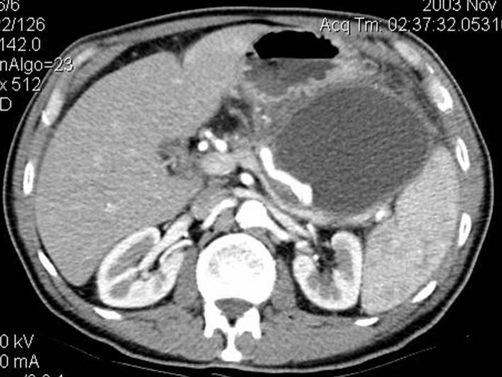

Puzzle 29

What's the Diagnosis?